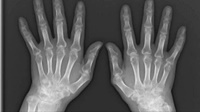

류마티스 관절염(RA)은 신체 전체에 관절통과 손상을 유발할 수 있는 자가 면역 질환입니다. 이 질환은 보통 신체 양쪽에서 동일한 관절에 영향을 주기 때문에, 한쪽 팔이나 다리의 관절이 영향을 받으면 반대쪽도 동일한 영향을 받을 수 있습니다. 이러한 특징은 의사들이 류마티스 관절염을 다른 형태의 관절염과 구별하는 데 도움이 됩니다.

조기에 진단할수록 치료 효과가 크기 때문에, 류마티스 관절염의 초기 증상을 알고 있는 것이 매우 중요합니다. 이 질환은 활막이 존재하는 모든 관절에서 발생할 수 있으며, 자가면역 이상으로 인해 외부 공격으로부터 신체를 보호하는 면역체계가 오작동하게 됩니다. 우리나라에서는 전체 인구의 약 1%가 류마티스 관절염을 앓고 있는 것으로 알려져 있습니다. 초기 증상은 눈에 잘 띄지 않으며, 통증과 뼈마디 변형이 발생한 후에야 발견될 수 있습니다.